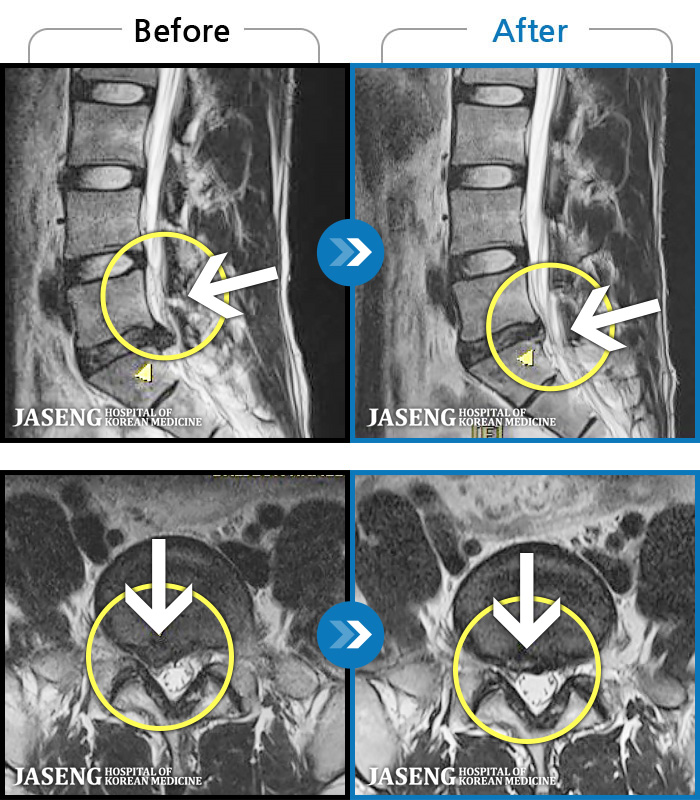

허리디스크

광주 · 김동은 원장

허리 양측 둔부에서 발가락으로 통증, 비증, 힘이 빠지는 증상

촬영시기

2018.08.11 ~ 2019.03.27

2019.04.25

조회수 18,503